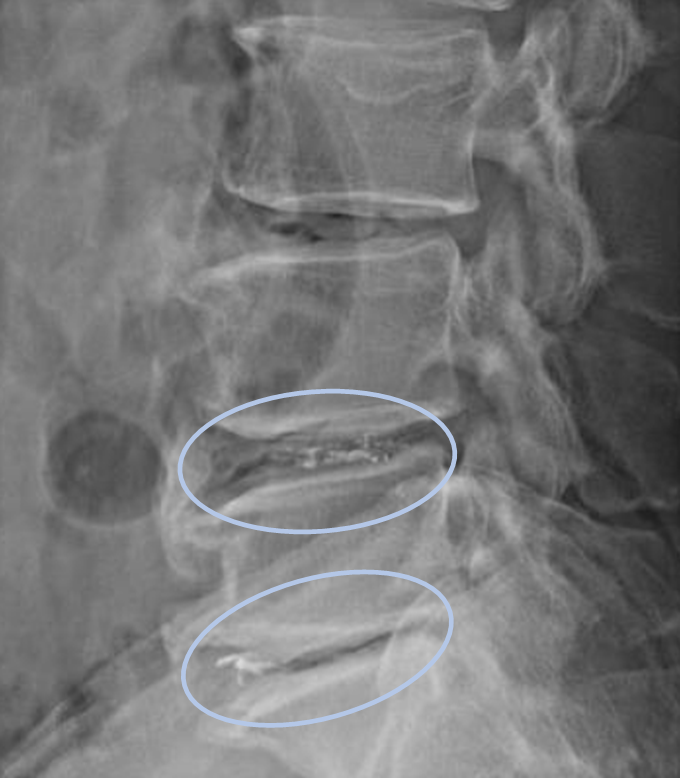

DiscoGelを入れた後の画像になります。

治療は25分程度で終了

回復室で休憩後、歩いて帰院されました。